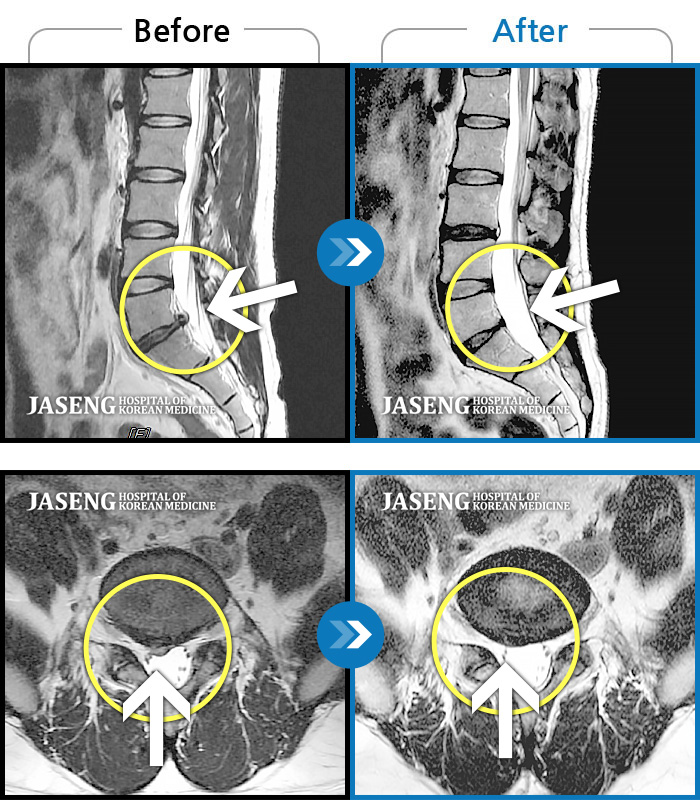

MRI 결과는 추간판협착증 2군데와 추간판탈출되어 터져서 디스크가 좌측으로 흘러내려 좌측 신경을 넓게 누르고 있는 곳이 1군데로 예상보다 심각한 상태였더군요.